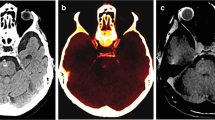

Calcium suppression in DECT used to generate VNCa images had been used for detecting bone marrow edema in vertebral fractures [27]. Images with higher calcium suppression index were found to detect bone marrow edema in fractures better. In the setting of iodine contrast-enhanced DECT, reconstructed images using lower calcium suppression indices were found to be more sensitive for detecting skeletal metastasis, which appeared as more hyperattenuating compared to surrounding tissue in VNCa images. In a retrospective study consisting of 21 patients with MRI-confirmed vertebral metastasis, the detection accuracy of iodine contrast-enhanced multi-level VNCa images was compared to conventional monoenergetic CT [12]. Images were reconstructed with low, medium, and high calcium suppression index. Low and medium calcium suppressed images were found to be more discriminatory of metastatic versus normal bone, as compared to high calcium suppressed images and conventional imaging. The sensitivity of detecting skeletal metastasis on low calcium suppressed images was also better (85%) compared to monoenergetic CT (78%). The authors attributed this finding to the similar attenuation profiles of calcium and iodine. In image maps reconstructed with higher calcium suppression levels, iodine was suppressed as well, and this decreased the iodine enhancement of metastatic lesions. In another small retrospective study, color mapping of bone marrow improved sensitivity of detecting skeletal metastasis from 78.2% on conventional CT to 89.8% [25]. The authors emphasized the importance of correlation with monoenergetic CT images, as two solely cortical lesions in the study were missed on the bone marrow color map images. Figure 2a–c and Fig. 2e–g are DECT images from our institute obtained on a patient with small cell lung cancer. The images illustrate the appearances of a L1 pedicle metastatic lytic lesion compared to T10 degenerative end plate erosions. Color-coded VNCa overlay reconstructions are shown in Fig. 2c and Fig. 2g. PET-CT axial images obtained 7 months earlier at the level of the L1 pedicle metastasis and T10 degenerative endplate erosion are shown in Fig. 2d and Fig. 2h, respectively.

Axial contrast-enhanced CT scan of a woman in her 60 s with small cell lung cancer metastasis. Right L1 pedicle metastasis (thick hollow arrow) in a bone window, b soft tissue window, and c color-coded VNCa overlay showing increased attenuation in the lesion (appearing green) and the d PET-CT performed 7 months earlier. Comparative appearance of a T10 vertebra degenerative end plate erosion (thin arrow) in the same patient in e bone window, f soft tissue window, and g color-coded VNCa overlay showing no increase in attenuation and the appearance on the earlier h PET-CT at the level of the T10 end plate erosion